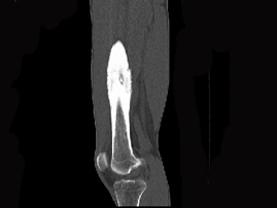

问题 患者,男,23岁,左大腿远端疼痛,夜间明显,服阿司匹林可缓解,请结合所提供图像,选择最佳答案 ( )

选项 A、骨巨细胞瘤 B、骨肉瘤 C、骨样骨瘤 D、骨化性纤维瘤 E、骨脓肿

答案 C